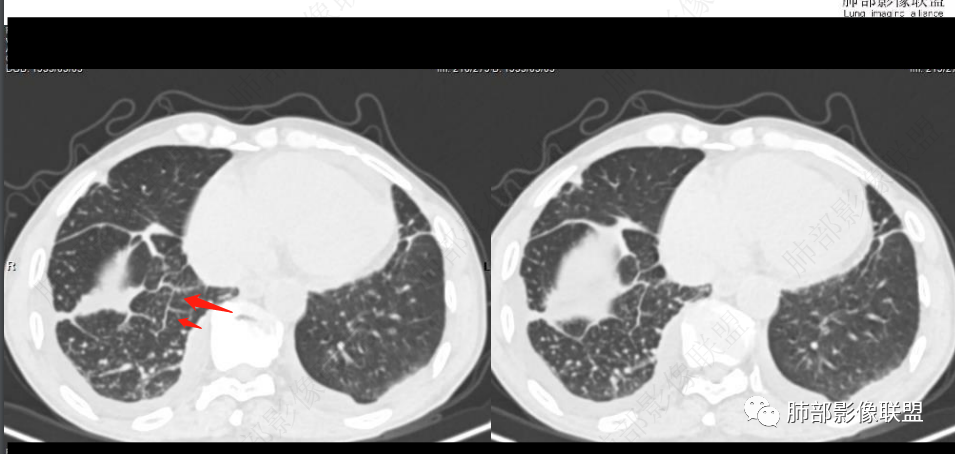

双肺叶透亮度呈磨砂状,并弥漫性以肺腺泡为单位GGO结节,边缘模糊,肺动脉高压表现,双肺下叶肺动脉分支明显增粗>邻近支气管径,小叶间隔增厚,叶间积液和少量胸腔积液,方向1.PVOD病并肺泡出血,2.心衰表现!

老年男性,胸闷、浮肿10天,左肺尖可见肺大泡影,两肺散在纤维索条影,右肺见弥漫性腺泡结节,以右肺上叶为著,右肺下叶局部小叶间隔增厚,双侧胸腔、右侧叶间裂及心包积液,结合实验室及影像检查,符合心衰及肺水肿表现,右肺部病变符合PVOD表现。

两边血管不对称,栓塞先考虑

左肺明显肺野透亮度增加,右肺明显肺水肿!右肺血管束稀疏,D二聚体明显高!首选左肺肺栓塞可能

老年女性,胸闷,水肿,气短,bnp高,临床有心功能不全,心彩无左衰依据,胸部ct右肺磨玻璃,小结节,小叶间隔增厚,血管不对称,考虑pe

肺水肿有的,可能心源性的,但导致的原因仍需进一步排查,虽有肾功能但不像肾源性,虽有肺动脉高压,但不考虑PVOD(年龄,性别,肺动脉高压可能由于瓣膜,心衰继发)。二聚体高,右肺胸膜下反晕病灶,肺梗要排除。另外就是右单肺腺泡结节以及带晕的实性结节。这个怎么解释。虽有误吸危险因素,但临床没有发热,血象不高。

看一下影像,肺动脉粗大,大于升主动脉

从肺动脉的主体分析:左肺动脉好像起始部就开始狭窄。

现在给的图像:是鼠尾状狭窄,而不会局部膨隆,远端细小那种。

右侧的肺动脉增粗肯定与代偿有关。

现在的问题是自左肺动脉狭窄的原因:是急性栓塞?炎性病变?慢性血栓?

2.右肺广泛密度增高、腺泡结节样磨玻璃影,血管影明显扩张,小叶间隔增厚。

4.左肺相对广泛低密度、血管纤细(显著)。